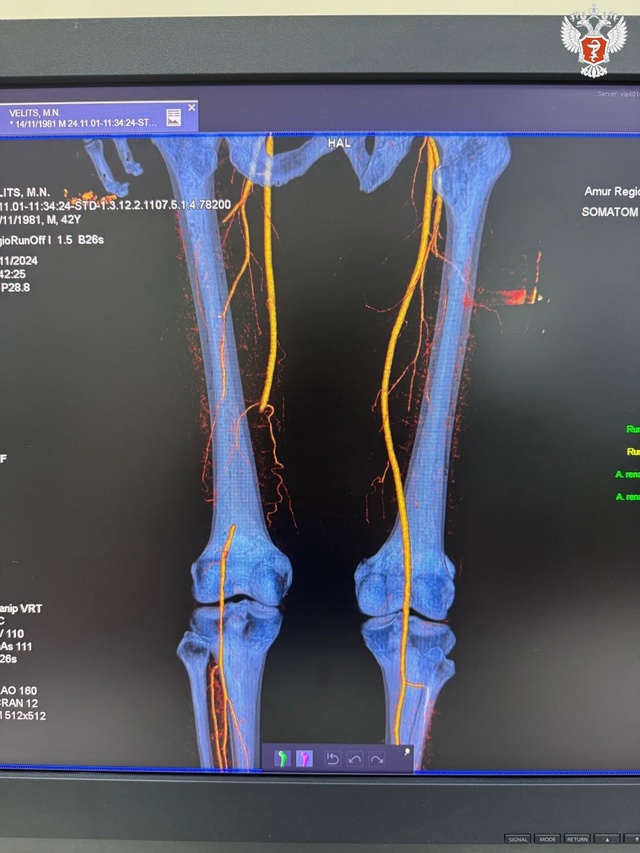

📄 Амурские врачи запатентовали новый метод профилактики рестеноза после шунтирующих операций на артериях нижних конечностей

Пациенты с атеросклерозом часто нуждаются в проведении повторных операций: кровь перестает нормально циркулировать, и сосуды могут вновь зарастать. Чтобы новая ткань не нарастала в местах контакта протеза с артерией, команда специалистов Амурской ГМА Минздрава России решила использовать препарат, угнетающий рост клеток.

Специалисты проводили операции с применением новой методики на базе кардиохирургической клиники Амурской ГМА Минздрава России и отделения сосудистой хирургии Амурской ОКБ. По итогу трех лет наблюдений отмечается, что большей части пациентов повторные операции не понадобились.